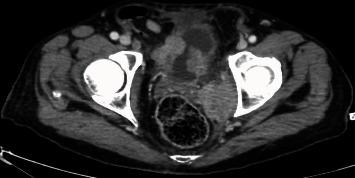

Large cell neuroendocrine carcinoma (LCNC) is one of the rarest types of bladder cancer occurring in <1%. Either pure or mixed with another component, it remains one of the most aggressive types of bladder cancer. We report a case of LCNC of the bladder with an adenocarcinomatous component. The patient was a 64-year-old smoker male, who presented for the first time with dysuria and hematuria. A bladder tumor invading the anterior and right lateral bladder walls was discovered, without any secondary localizations. Tumor biopsy showed an LCNC with adenocarcinomatous components. The patient was treated by recurrent tumor resections, chemotherapy, and radiotherapy. No improvement was noted despite close follow-up and adequate treatment. Neuroendocrine bladder tumor is known to have an aggressive, rapid, and disadvantageous evolution. Multiple case reports were published so far, and a recent review was conducted in March 2020 by Sanguedolce et al. (2020). More cases are needed to establish the best management plan for this type of tumor.

大细胞神经内分泌癌(LCNC)是最罕见的膀胱癌类型之一,发病率低于1%。无论为单纯型还是与其他成分混合型,它始终是最具侵袭性的膀胱癌类型之一。我们报告一例伴有腺癌成分的膀胱LCNC病例。患者为一名64岁男性吸烟者,首次因排尿困难和血尿就诊。发现一个侵犯膀胱前壁和右侧壁的膀胱肿瘤,无任何继发性定位。肿瘤活检显示为伴有腺癌成分的LCNC。患者接受了复发性肿瘤切除术、化疗和放疗。尽管进行了密切随访和充分治疗,但未见改善。已知神经内分泌膀胱肿瘤具有侵袭性、快速且不利的病程。迄今为止已发表了多篇病例报告,Sanguedolce等人于2020年3月进行了一项最新综述。需要更多病例来制定针对此类肿瘤的最佳管理方案。